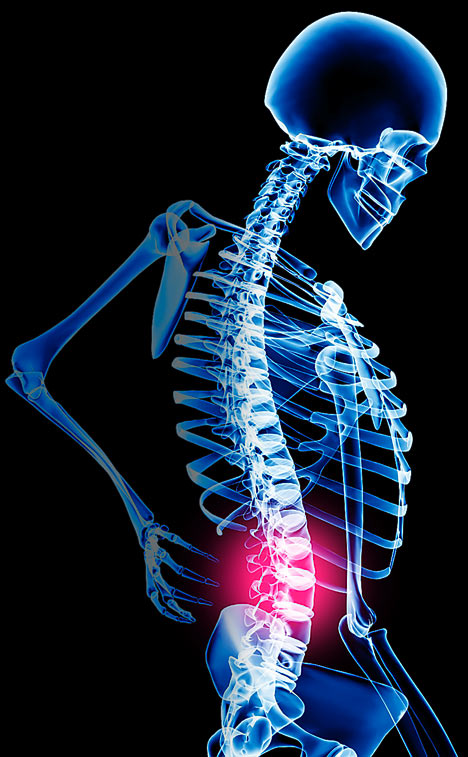

Οσφυαλγία: η πιο κοινή αιτία επίσκεψης σε γιατρό

Η οσφυαλγία (πόνος στη μέση) είναι μία ενοχλητική κατάσταση (σύμπτωμα) που «προσβάλει» το 90% του ενήλικου πληθυσμού μία φορά σε κάποια στιγμή της ζωής του. Σε ποσοστό 50% υπάρχουν περισσότερα από ένα επεισόδια οσφυαλγίας.

Πρέπει να πούμε ότι η οσφυαλγία είναι ένα γενικό σύμπτωμα που μπορεί να οφείλεται σε διάφορα αίτια και να απασχολεί διαφορετικές ιατρικές ειδικότητες.

ΣΗΜΕΙΩΤΕΟΝ ΟΤΙ Η ΟΣΦΥΑΛΓΙΑ ΕΙΝΑΙ Η ΠΙΟ ΚΟΙΝΗ ΑΙΤΙΑ ΕΠΙΣΚΕΨΗΣ ΤΟΣΟ ΣΕ ΙΔΙΩΤΙΚΟ ΙΑΤΡΕΙΟ ΟΣΟ ΚΑΙ ΣΤΟ ΤΜΗΜΑ ΕΠΕΙΓΟΝΤΩΝ ΠΕΡΙΣΤΑΤΙΚΩΝ ΣΤΑ ΝΟΣΟΚΟΜΕΙΑ.

Από τις συχνότερες αιτίες οσφυαλγίας είναι η κήλη μεσοσπονδυλίου δίσκου. Ο μεσοσπονδύλιος δίσκος είναι μία «ειδική δομή» μεταξύ δύο σπονδύλων αποτελούμενος στο κέντρο από τον πηκτοειδή πυρήνα και στην περιφέρεια από τον ινώδη δακτύλιο. Η χρησιμότητά του είναι να λειτουργεί ως «αμορτισέρ» απορροφώντας τους κραδασμούς κατά τις κινήσεις της σπονδυλικής στήλης. Κήλη μεσοσπονδυλίου δίσκου είναι η προβολή (μετατόπιση) τμήματος του κεντρικού πηκτοειδούς πυρήνα προς την περιφέρεια. Αυτό έχει σαν αποτέλεσμα προβολή του ινώδους δακτυλίου και δημιουργία κήλης, που τις περισσότερες φορές πιέζει κάποιο νεύρο έτσι ώστε εκτός από οσφυαλγία να υπάρχει και πόνος στη διαδρομή του πιεσμένου νεύρου σε κάποιο πόδι.